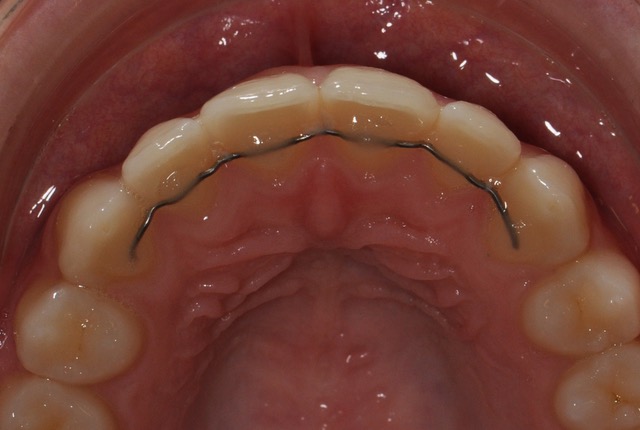

Sogenannte Retainer (Synonyme: Zahnstabilisator, Retentionsgerät) sollen die Resultate kieferorthopädischer oder kieferchirurgische Behandlungen erhalten. Will heissen: ein Draht wird, von aussen her unsichtbar, hinter die Zahnbogen geklebt, damit die schön aufgereihten Zähne genau so stehen bleiben. Es gibt verschiedene Materialien und Klebetechniken (in der Regel wird die Befestigung von Eckzahn zu Eckzahn angebracht).

Von einem Rezidiv Betroffene haben Zeit und Geld investiert und oft auch Schmerzen durch Spangen oder Operationen erlitten. Doch bei ihnen ging der Retainer kaputt (bei einer Patientin gar dreimal) oder die Zähne verschoben sich samt geklebtem Draht wieder in eine unerwünschte Richtung. Verantwortlich dafür sind meist die sieben Muskeln der Zunge. Sie haben eine so gewaltige Kraft, dass sie diese Drähte sprengen können.

Die Zungenspitze sollte in der Zungenruhelage oben hinter den Schaufelzähnen liegen kommen und wie der Name besagt, dort ruhen. Meist wird sie aber vom Retainer regelrecht angezogen. Wie wenn ein Stückchen Fleisch zwischen den Zähnen hängen bleibt, wird die Zungenspitze reflexartig animiert, an diesem Fremdkörper herumzuzüngeln. Es entsteht ein unruhiger Mund (restless mouth) und damit ein oraler Habit. Habits sind Gewohnheiten rund um den Mund, für welche die Regel gilt: Habits verunmöglichen ein stabiles, korrektes Schluckmuster.

Meine Patienten mit Rezidiven zeigen ausnahmslos ein falsches Schluckmuster: dabei gehen die Kräfte der Zunge nicht nach oben in den Gaumen, sondern nach vorn an die Schaufelzähne und somit an den Retentionsdraht. So kann dieser kaputt gehen, denn wir schlucken am Tag zweimal pro Minute und nachts einmal. Diese Kräfte sind ungeheuer gross; man sagt 4000kg auf 24 Stunden: die Zunge als Draht-Sprenger oder Beisszange.